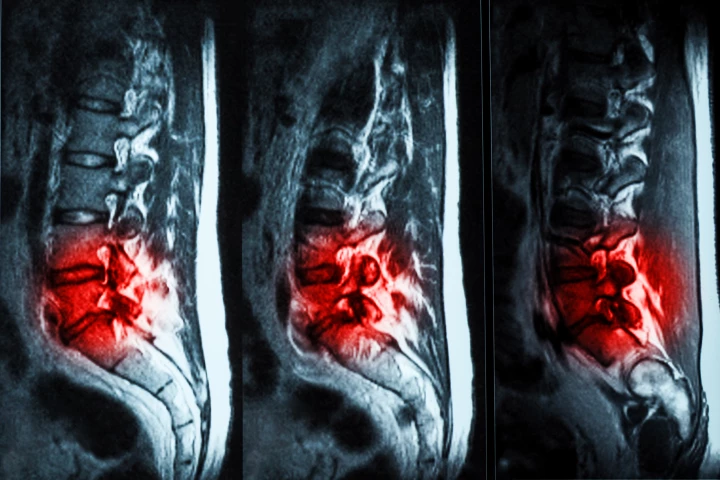

Back Pain

In big news for the millions who suffer from chronic lower back pain due to degraded disks, scientists have made a potentially huge breakthrough in understanding its cause at a microscopic level, paving the way for effective cell therapy to relieve it.

Sufferers of chronic lower back pain know there's no magic bullet when it comes to easing the often debilitating symptoms of degenerative disk disease. But new regenerative cell therapy delivered with a single injection is hoping to be just that.

Human trials have shown that hydrogel injections are a promising, effective treatment for chronic lower back pain caused by degenerative disc disease (DDD). The treatment is far less invasive than other surgeries, and has been given FDA approval.